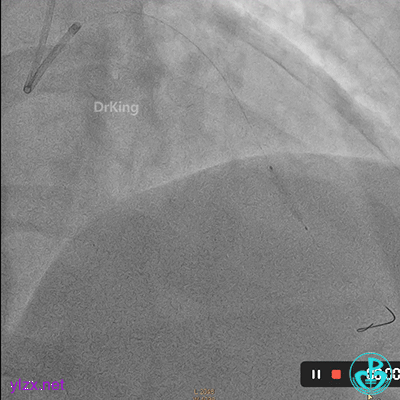

08 1个月后复查

RCA粗大全程瘤样扩张明显,自近段闭塞,TIMI血流0级;可见自身桥侧支逆供RCA远段。

LM未见明显狭窄,LAD开口至近段明显瘤样扩张,自近段闭塞,TIMI血流0级,D1瘤样扩张,TIMI血流2级;可见D1逆供LAD中远段及RCA中远段。

LCX发育小,内膜不光滑,TIMI血流3-级,逆供RCA中远段。